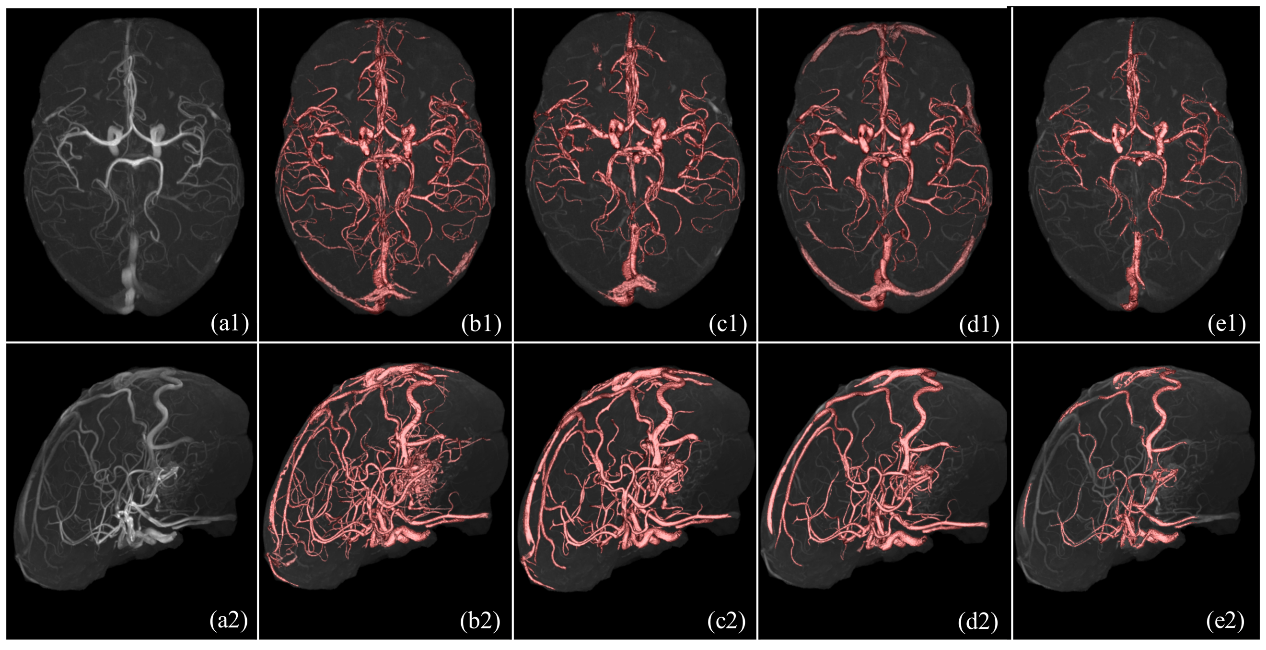

现有的各类脑磁共振血管分割方法依赖于特定MR成像设备或特定数据集,基于模型驱动的血管分割方法通常不能完整地提取脑血管网络并且存在过分割现象,基于深度学习的方法受限于海量数据标注问题。上述两篇论文分别提出了两种鲁棒的统计学方法,实现任意磁共振设备型号下的TOF-MRA三维数据的全脑血管拓扑结构精确提取(如图1、2、3),该研究可以对深度学习方法提供血管数据的自动标注工具;在特定磁共振设备下,实现基于三维TOF-MRA和MR-T1数据的完整脑动脉和脑静脉结构的精确分割(如图4(f))。上述成果对于脑血管的自动标注、分割、临床可视化具有重要现实意义。

图4. 由左至右为十套脑磁共振血管造影数据的分割结果:(a)原始TOF-MRA造影数据的最大密度投影视图;(b-e):4种对比方法;(f):本文所提方法;(g-h):动静脉分离结果